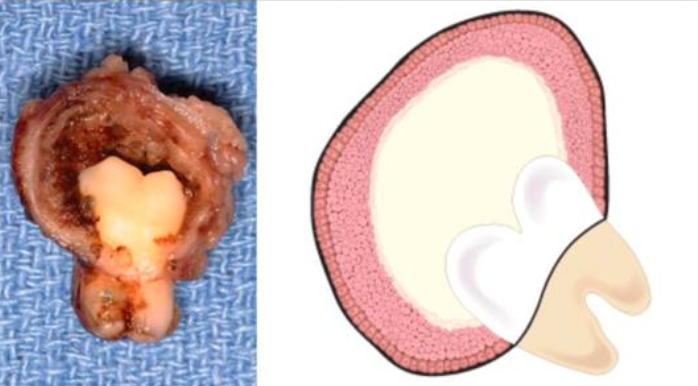

| Periapical(radicular) cysts | Rest of Malassez 被刺激 | - | - | true/ periapical cyst 圓形的光通性包圍根尖 |

牙根吸收, 2cm ↑ 根管治療無效  |